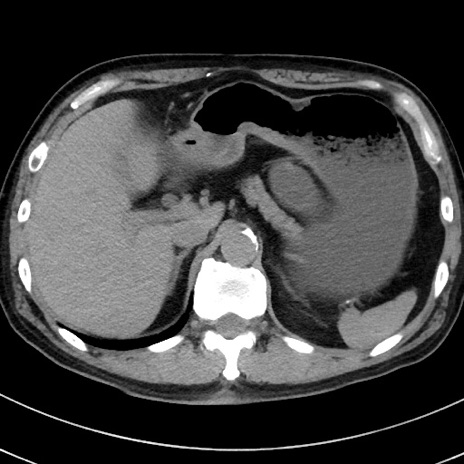

症例38(横断像)

【症例】70歳代 男性

【主訴】腹痛・嘔吐

【現病歴】昨晩より、嘔吐・腹痛あり。今朝になっても嘔吐あり。来院。

【既往歴】心臓バイパス手術、開腹胆摘、腸閉塞

【身体所見】BP 107/71mmHg、HR 116/min、腹部:平坦、軟、下腹部に軽度圧痛あり。反跳痛なし。

【データ】WBC 15100、CRP 0.32